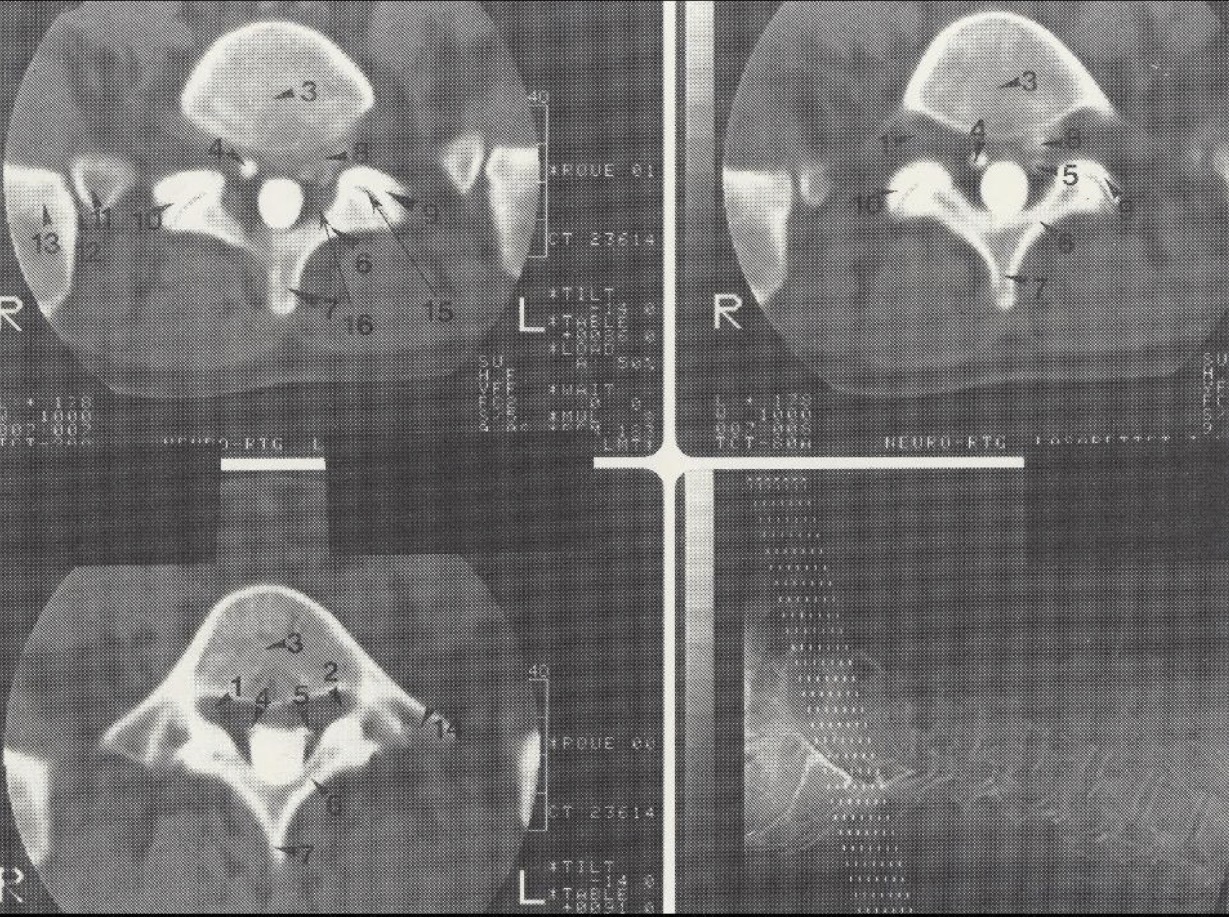

1

Dešinioji L 5 šaknelė

2

Kairioji L 5 šaknelė

3

Corpus vertebrae L V

4

Dešinioji S 1 šaknelė

5

Kairioji S 1 šaknelė

6

Lamina L V

7

Processus spinosus L V

8

Disko išvarža (tarp L V ir S I, spaudžianti kairiąsias L 5 ir S 1 šakneles)

9

Processus articularis superior sinister S I

10

Processus articularis superior dexter S I

11

Os sacrum (pars lateralis)

12

Articulatio sacroiliaca

13

Os ilium

14

Processus transversus L V

15

Tarpslankstelinė anga (tarp L V ir S I)

16

Ligamentum flavum (dešinėje pusėje sustorėjęs)